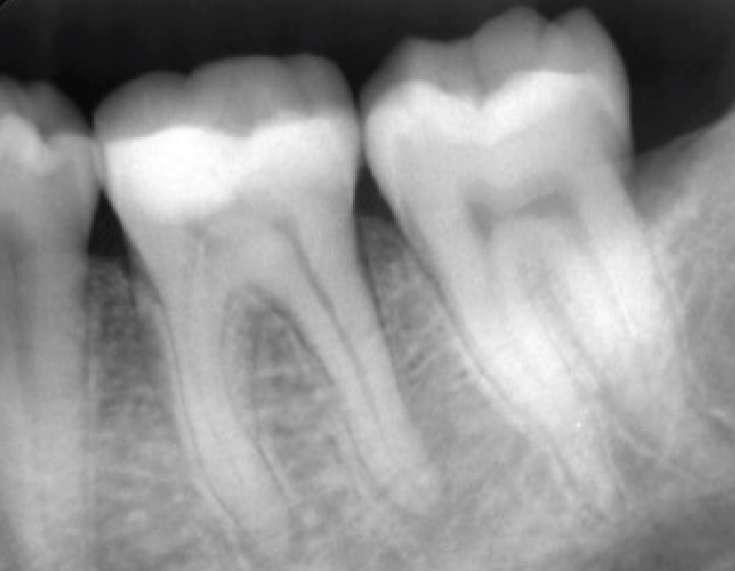

Vier Kanäle wurden mit dem SX EdgeTaper Platinum eröffnet. Auch der koronale Teil wurde mit dem S1 EdgeTaper Platinum erweitert. Arbeitslänge und Durchgängigkeit werden mit einer #10 K-Feile erreicht. Die A #15 K-Feile wurde verwendet, um Länge und Durchgängigkeit zu gewährleisten. Dank der Technologie von EdgeNedo war ich im Stande, die Feile für eine komfortable Formgebung vorzuformen, auch wenn die Öffnung reduziert wurde. S1, S2, F1 und F2 EdgeEndo Platin wurde bis zur gesamten Länge des Kanals eingebracht.

Während der Isthmus-Reinigung zeigte sich zwischen den mesialen Kanälen ein zusätzlicher Kanal. Die Formgebungsphase erfolgte schnell und effizient dank SX zum F2.

Das Röntgenbild zeigte eine große Länge und einen gemeinsamen Ausgang für zwei der drei mesialen Kanäle.

Die Wurzelfüllung erfolgte mit einer einzigen Kegeltechnik unter Verwendung des BUSA EndoSequence Bioceramic Sealer. Das Post-OP-Röntgen zeigt sehr hohe Dichte in der gesamten Länge der Wurzelfüllung.